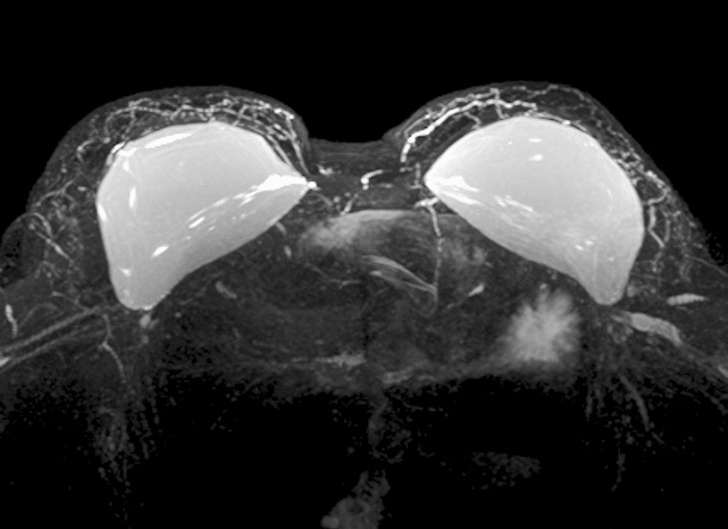

6. Силіконові груди в апараті МРТ